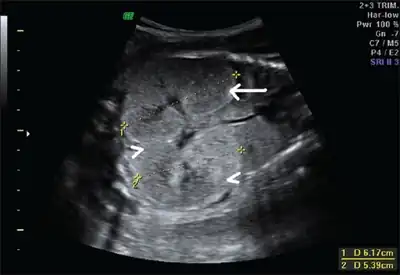

Ultrasonography is the primary method to evaluate autosomal recessive polycystic kidney disease, particularly in the perinatal and neonatal stages.[3]

Fetus with bilateral enlarged/hyperechogenic kidneys arrow & diminished cortico-medullary differentiation arrowhead -